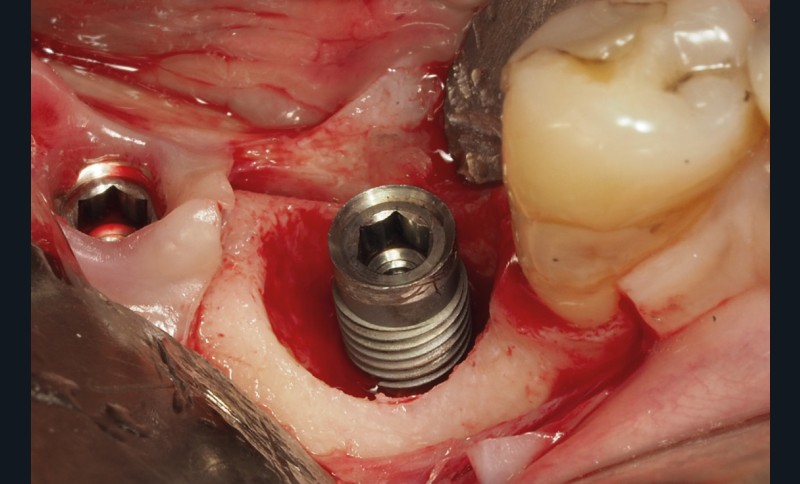

De nombreuses approches ont été décrites, mais le principal objectif de la chirurgie est de créer un accès à la surface implantaire, d’éliminer le biofilm, les dépôts calcifiés et, peut-être, les excès de ciment. La décontamination de la surface implantaire doit permettre d’arrêter la progression de la maladie et d’obtenir la cicatrisation de la lésion [8]. Des techniques régénératives ont également été décrites, celles-ci ont pour objectif de réparer le défaut intra-osseux et de permettre une ré-ostéointégration de la surface implantaire [9].

La chirurgie résectrice a pour objectif de permettre la décontamination de la surface implantaire et la modification de la morphologie des tissus péri-implantaires afin de faciliter le contrôle de plaque quotidien [8]. Cela implique l’élimination du tissu de granulation, un repositionnement apical du lambeau muco-périosté et d’éventuelles ostéoplasties et ostéotomies [10].